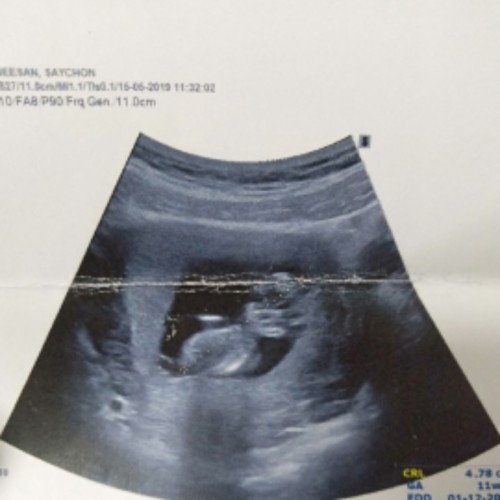

อันนี้ชาวตอน11วีคค่ะ ปัจจุบัน16วีคแล้วว